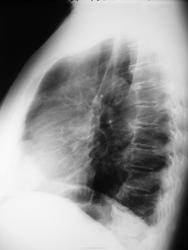

Пневмония? Локальный фиброз?

Пациентка около 65 лет с жалобами на слабость, повышение температуры в течение 2 дней направлена с д-зом ОРВИ. Пневмония?

Предыдущее исследование ОГК (ФЛГ) выполнялось в ноябре 2012 г

пусть будет пневмония, хотя на боковом не сыщешь )

Я бы написала в заключении очаговую пневмонию в S4.

По мне - так нет. Пневмосклероз, может дисковидный ателектаз.

Примерно так + локальное усиление легочного рисунка, уплотнение главной междолевой плевры.

Думаю, право на жизнь имеет версия двусторонней интерстициальной пневмонии. ОРВИ нижнего респираторного тракта.